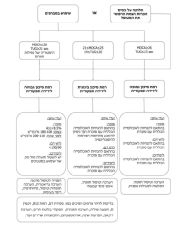

| 08:30, 16 בספטמבר 2023 | לוואי מאוחרות1.png (קובץ) |  |

590 קילו־בייטים | Motyk | 1 | |